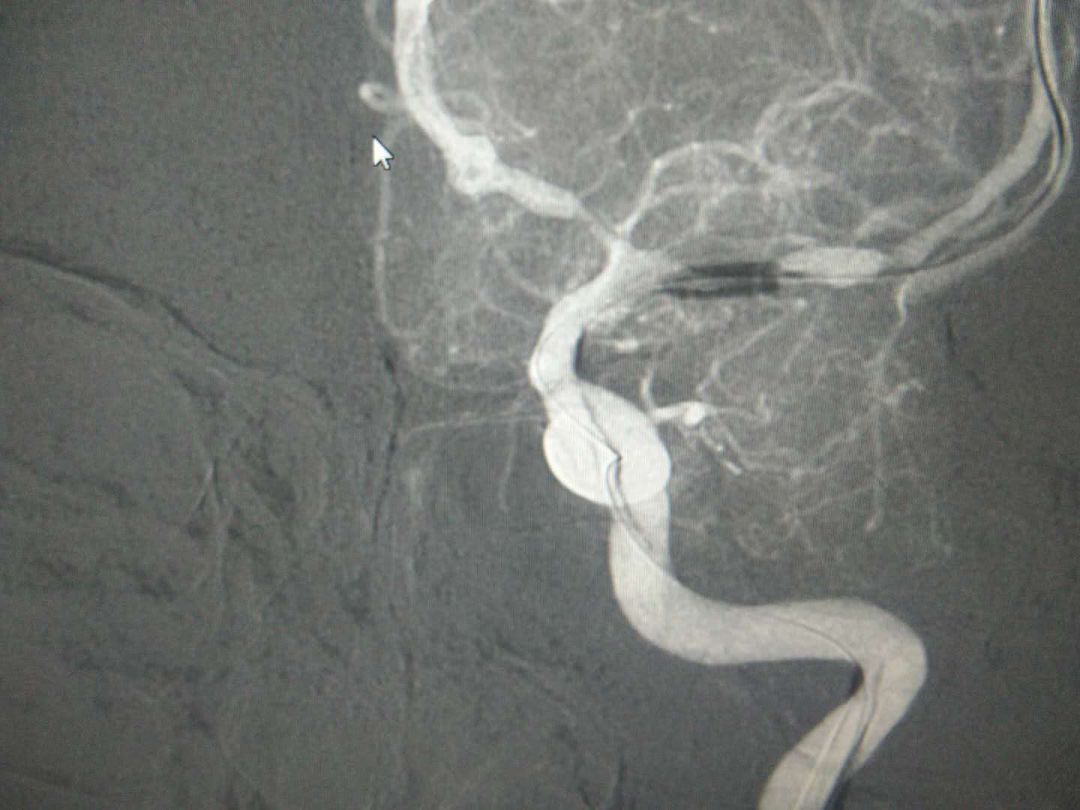

图片

(支架释放前)

(支架扩张中)

(支架释放后)